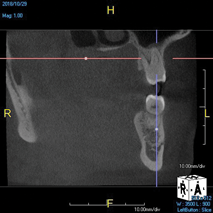

(8.) An original finding of a small lesion on the mesial root of tooth No. 30 was not accompanied by any outward symptoms; therefore, the patient delayed pursuing treatment. When a follow-up CBCT scan was acquired 6 years later, the easy-to-visualize increase in the dimensions of the lesion motivated the patient to elect a treatment plan.

Figure 8

(9.) An original finding of a small lesion on the mesial root of tooth No. 30 was not accompanied by any outward symptoms; therefore, the patient delayed pursuing treatment. When a follow-up CBCT scan was acquired 6 years later, the easy-to-visualize increase in the dimensions of the lesion motivated the patient to elect a treatment plan.

Figure 9